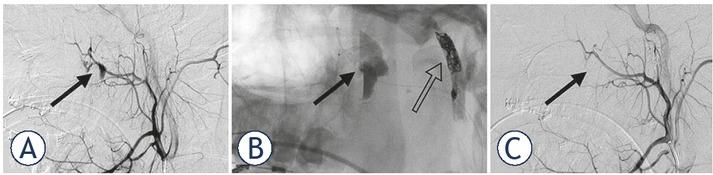

The patient was transferred to the neurointerventional suite and a standard right transfemoral vascular access was established. Digital substraction angiography (DSA) showed a laceration of the left ECA with an ensuing 3 × 4 cm pseudoaneurysm continuing into the proximal part of the left IMA (Figure 3A). DSA also showed a right SPA laceration with two small accompanying pseudoaneurysms (Figure 4A). The two culprit arteries were then superselectively catheterized and embolized. ECA embolization was performed using platinum coils and PHIL 25, while the SPA was embolized with PHIL 25 only (Figures 3B and 4B). In the case of the ECA embolization, coils created a mesh scaffold acting as a thrombogenic locus, and PHIL was then added to form a coagulopathy-independent lumen-obliterating cast. PHIL was chosen over other available liquid EAs for its ready-to-use characteristics, saving precious time in an emergency setting. In addition, its lava-like polymerisation properties ensured a well-controlled application, helping prevent any inadvertent injection into the dangerous ECA-internal carotid artery and ECA-vertebral artery anastomoses.

(A) A lateral right ECA angiogram showing two pseudoaneurysms in the region of the right pterygopalatine fossa and nasal cavity (black arrows). (B) Fluoroscopy showing microcatether proximally to the hematoma in the right pterygopalatine fossa (black arrow) prior to PHIL 25 application. Also visible is the embolized contralateral ECA (empty arrow). (C) A post-embolization right ECA angiogram showing complete sphenopalatine artery occlusion (black arrow). Also visible are the patent vessels proximally to the embolization.

Effort was made to embolize at or just proximal to the laceration point in order to preserve proximal arterial territories. Embolization was continued to the point of arterial stasis. Due to the well-developed left ECA and the resulting high blood flow to the pseudoaneurysm, the ECA embolization was performed under flow control provided by temporary proximal balloon occlusion. No flow control was needed for the SPA embolization. The embolizations of both lesions were immediately followed by complete cessation of the ear bleeding.

Postembolization imaging showed total exclusion of the lacerated vessels (Figures 3C and 4C), complete patency of all proximal vessels, no collateral pathways to the pseudoaneurysm and no other origins of bleeding. There were no procedure-related complications.